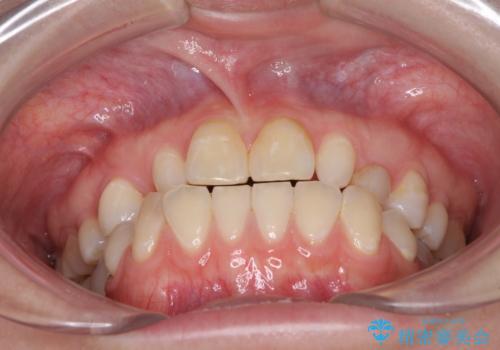

欠損と残存乳歯 矯正治療とインプラント治療

- 残存した乳歯や歯の欠損、歯並びを気にして来院された患者様です。

乳歯を残した状態は予後がよくないこと、矯正治療と補綴治療を総合的に進めていきたいとのことで、インビザラインによる矯正治療とインプラント補綴治療を並行して進めていくこととしました。

当院は矯正治療もインプラント補綴治療も、同一の歯科医師が担当するため、矯正治療を行いながら、最適なタイミングでインプラント補綴治療を行うことが可能です。